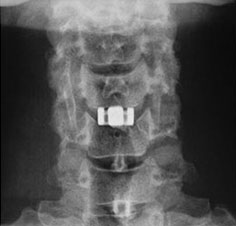

レントゲン 正面像

脊椎・脊髄疾患 : 頚椎前方除圧固定術(ケージを使用した手術)

頸椎症や、頚椎椎間板ヘルニアで神経を圧迫している部分が、神経より前方(のど側)にある場合に、のどのあたりから入って、あっぽあくの原因となっているものを取り除きます(除圧)。その後、除圧した上下の骨を固定します。その際チタン製のケージという医療材料を使用して、骨と骨が療合するまでの間の固定の補助とします。

椎間板が取り除かれたままでは、上下の骨がゆるい状態になるため、チタン製のケージを挿入し、上下の骨をしっかり固定します。

頚椎前方除圧固定術で使用するチタン製ケージ